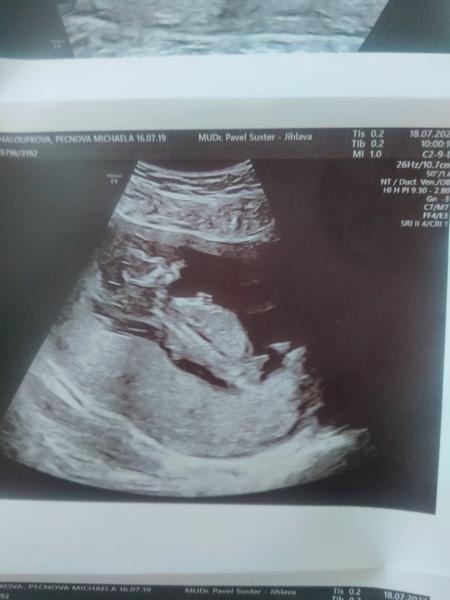

Taky kluk ❤️